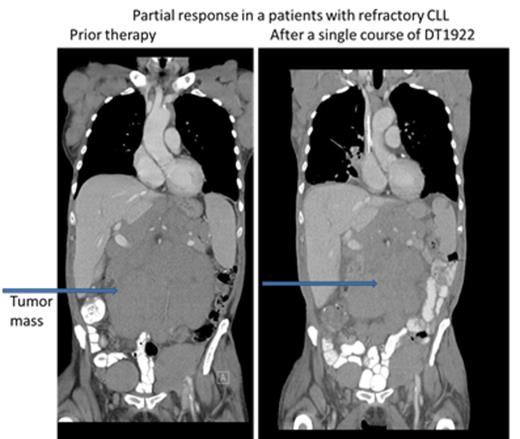

CT images of 77 year old patient with refractory CLL after a single course of DT1922 at dose level 40 µg/kg.

We conducted a phase 1 study to assess safety, to determine the maximum tolerated dose (MTD) and to evaluate preliminary efficacy in patients with chemotherapy refractory B cell leukemia or lymphoma expressing CD19 and/or CD22. DT2219 was administered in a single course intravenously over 4 hours (1-2 hours for subsequent doses) every other day for 4 total doses. The starting dose was 0.5 µg/kg/dose (2.0 ug/kg/course) (1/1000th of the MTD in rabbits). The dose was escalated by accelerated design until dose limited toxicity (DLT) was observed. Twenty-two patients were enrolled, with a median age of 55 years (range, 34-78). Five patients had pre-B acute lymphoblastic leukemia (4 refractory, 1 with extra-medullary disease, 1 had chronic lymphocytic leukemia (CLL) and 7 had non-Hodgkin lymphoma). All were chemo-refractory with a median of 4 prior therapies. All patients had biopsy-confirmed tumor expression of CD19 and/or CD22. The first 9 patients were treated at doses ranging from 0.5 ug/kg/dose to 20 ug/kg/dose. No drug was detectable in those patients and they experienced no DLT or clinical responses. DT2219 was detectable in the serum at doses ≥40 µg/kg/dose (N=13). Dose levels were 40 µg/kg/day N=5; 60 µg/kg/day N=5; 80 µg/kg/day N=3. The area under the curve (AUC ) range was 1,104 -1,346 and the half-life ranged from 54-84 minutes. After a single course of DT2219 we observed partial remission in a 77 year old patient with rituximab/chemotherapy-refractory CLL (dose level 40 µg/kg). The 40% reduction in the abdominal tumor mass is shown in Figure 1. This patient did not experience any DLT. A second partial remission was observed in 53 year old patient with relapsed marginal zone lymphoma (dose level 60 µg/kg) who experienced a DLT of capillary leak syndrome. After regulatory approval, that patient received a second treatment course 8 weeks later at a reduced dose of 40 µg/kg which resulted in a complete remission (Figure 2). Both patients are alive and in remission at 6 and 4 months, respectively, after therapy. Adverse events were observed in all patients who received ≥40 µg/kg. The most common was grade 1-2 capillary leak syndrome, grade 1-2 hematologic toxicity, elevated liver function tests and fatigue. Two patients experienced DLTs: at the 40 µg/kg dose (grade 3 lower extremity weakness) and 60 µg/kg dose ( grade 4 neutropenia and grade 3 capillary leak). All adverse reactions resolved completely within one week. Immunogenicity and formation of neutralizing antibodies is a major barrier in development of DT-based immunotoxins. Remarkably, none of the 8 patients with B-cell lymphoma/CLL who had received rituximab within weeks preceding therapy with DT2219 had detectable neutralizing antibody. These patients had no detectable B cells at the time of study drug administration. This suggests that rituximab pre-treatment may prevent the development of neutralizing antibodies and allow for repetitive dosing. In conclusion, we have demonstrated promising clinical efficacy of the novel immunotoxin DT2219 in refractory B cell lymphoid malignancies. We determined that the biologically active dose of DT2219 is between 40-80 µg/kg and that repetitive dosing is feasible in patients pre-treated with rituximab. Phase 2 trial is in development.